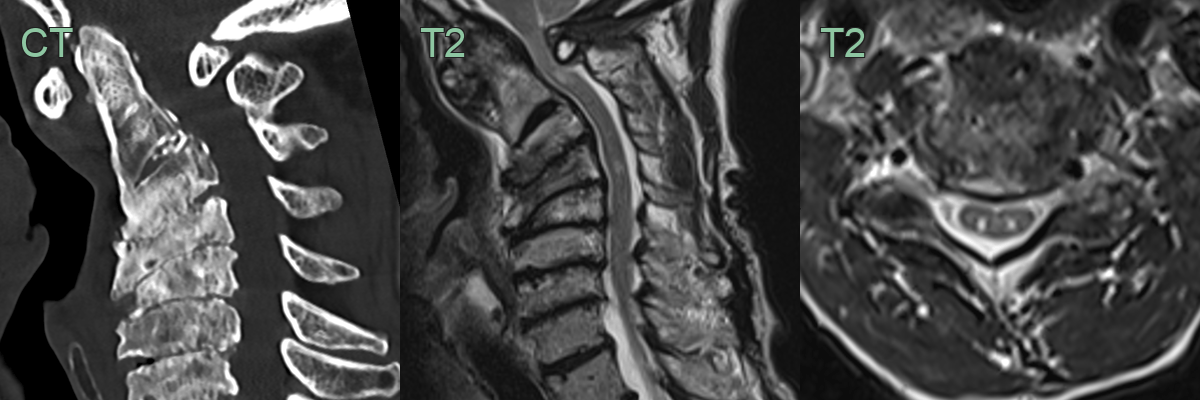

- Magnetic Resonance Imaging (MRI):

- Gold standard for diagnosis

- T2-weighted images: hyperintense signal within the cord

- T1-weighted images: assess for cord atrophy

- Computed Tomography (CT):

- Useful for assessing bony abnormalities

- CT myelography: alternative when MRI is contraindicated